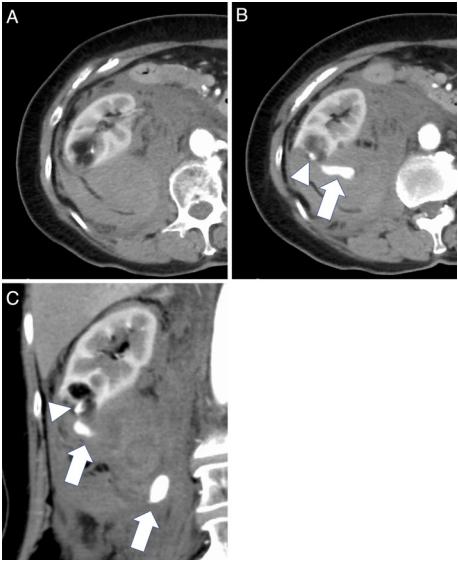

常规随访每6个月行双超检查,未见肿瘤生长或动脉瘤改变。然而,随访2年后,患者因急性右侧腹痛被送到急诊科。到达医院后,因血流动力学不稳定而神志不清;血压和脉搏80/50mmHg和120次/分钟。入院时血液检查显示血红蛋白水平为5.9 g/dL,血细胞比容17%,CECT显示腹膜后血肿(11×14×20cm),瘤内动脉瘤造影剂外渗5mm(图2)。患者被诊断为急性髓性白血病破裂,并立即转移到血管造影室进行TAE。

图2、入院时的对比增强计算机断层扫描(CECT)

图2A、2B的轴向横切面和图3C的冠状面横切面分别对应图1A、1B、1C的切片。CECT显示肾血管平滑肌脂肪瘤微动脉瘤(2B和2C,箭头)腹膜后血肿(11×14×20 cm)伴造影剂外渗(2B和2C,箭头)